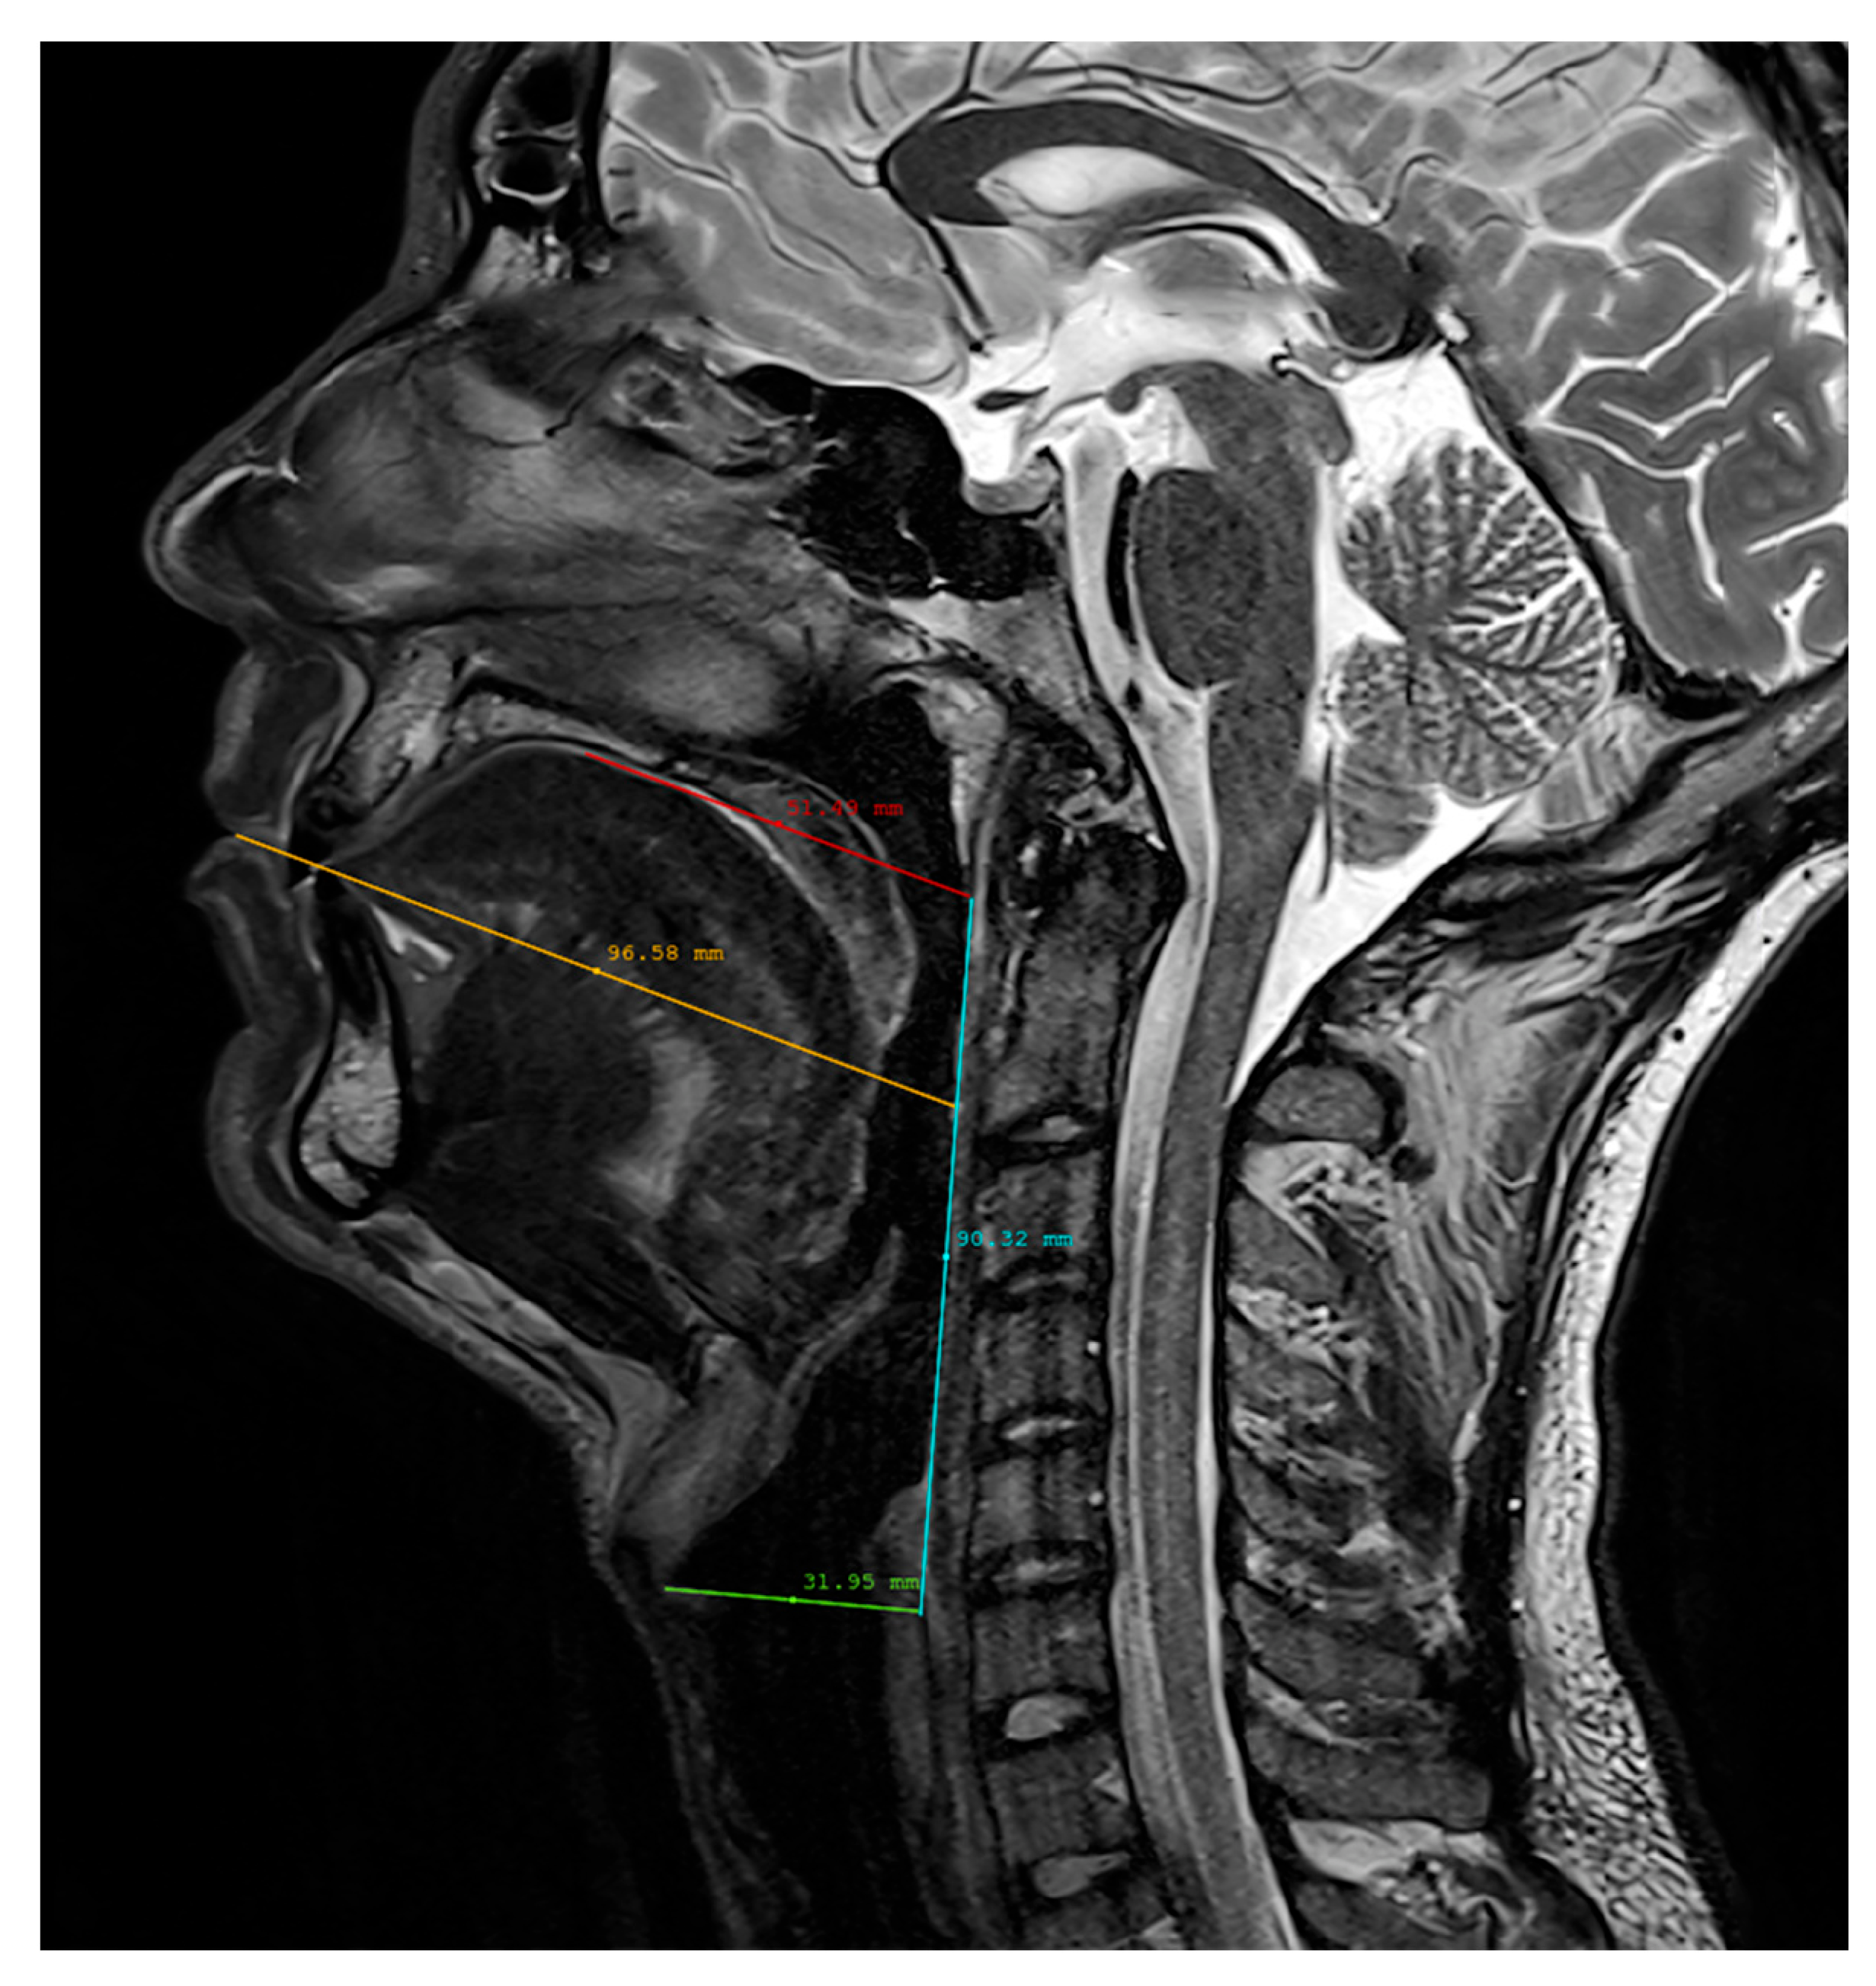

2.3. Vocal Tract Measurements

| Speaker | Length (mm) | Height (mm) | Width (mm) |

|---|---|---|---|

| SP1 | 97 | 92 | 40 |

| SP2 | 77 | 76 | 32 |

| SP3 | 99 | 81 | 40 |

| SP4 | 89 | 69 | 34 |

| SP5 | 94 | 86 | 36 |

| SP6 | 87 | 81 | 32 |

| SP7 | 88 | 90 | 38 |

| SP8 | 87 | 67 | 34 |

| Mean | 89.8 | 80.3 | 35.8 |

| SD | 6.5 | 8.6 | 3.1 |